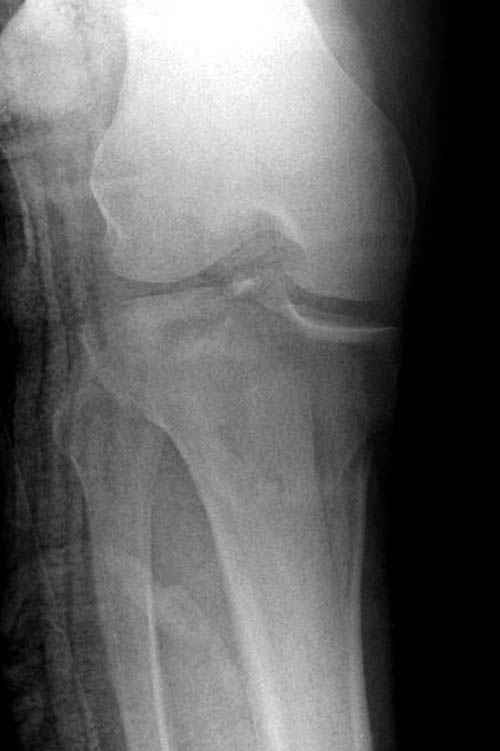

Трудно поверить, что разрекламированная Ортопедическая школа Восточной Украины позволяет такие странные снимки? На прямом снимке сохранен общий контур плато, но не известна судьба импрессии суставной поверхности. На полубоковой?, оставлен без репозиции задне-медиальный отдел, и навряд ли после такой фиксации можно удовлетвориться результатом.

Такая ситуация характерна для многих, когда принимается ошибочное решение, т.е пытаются фиксировать одним имплантом переломы двух мыщелков. Латеральная пластина приемлема только для тех случаев, когда сохраняется интактным медиальный диафизарный кортекс и отсутствует фрагментация на верхушке медиального перелома.

Здесь как раз тот случай, когда результат зависит не только от мастерства хирурга, но и от наличия современных методов исследования. Например, КТ которая поможет рассчитать направления шурупов и установку импланта. Кроме этого, поможет определиться с доступом.

Представленные снимки не информативны, нужны отдельные качественные снимки коленного сустава и голени без ротации.